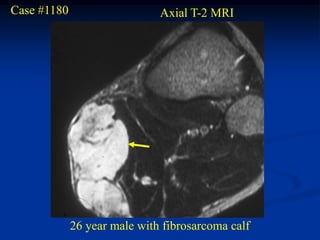

Case #1180                    Axial T-2 MRI

26 year male with fibrosarcoma calf

Case #1180 Axial T-2 MRI 26 year male with fibrosarcoma calf